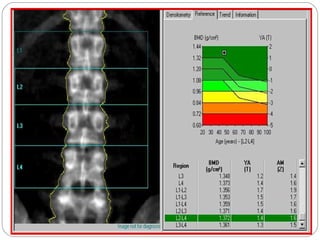

DEXA SCAN

Looks at bone mineral densities

DEXA SCAN Looks atbone mineral densities